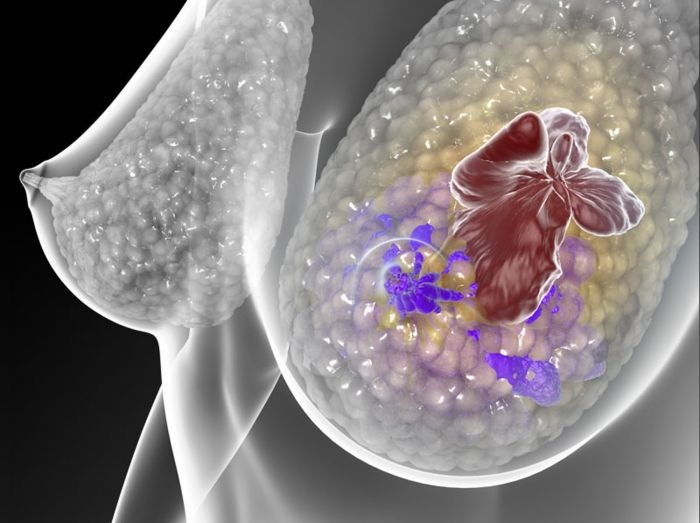

Neste 8 de março, Dia Internacional da Mulher, uma audiência pública na Assembleia Legislativa do Rio Grande do Sul irá debater assunto essencial para muitas mulheres no estado: as condições atuais de acesso a tratamentos inovadores, pelo SUS (Sistema Único de Saúde), para o câncer de mama metastático. De acordo com dados do Inca (Instituto Nacional do Câncer) de 2016, Porto Alegre é a capital com maior incidência de câncer de mama no Brasil, com 130 casos registrados para cada 100 mil habitantes ? a média nacional entre capitais é de 79 casos para cada 100 mil habitantes.